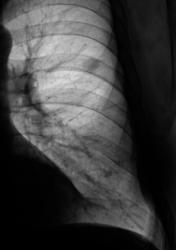

2009 г.

Окружающая легочная ткань - 2008 и 2009 г.

Вердикт диспансера - "наблюдение в динамике".